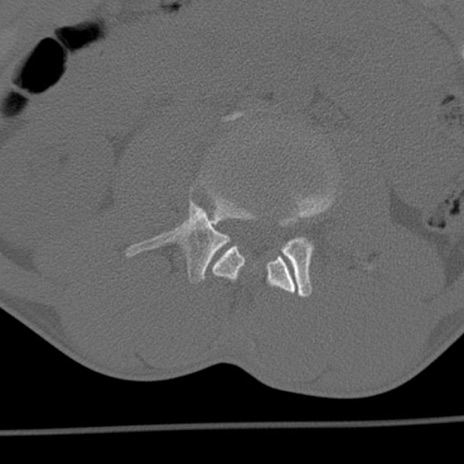

症例3 腰椎CT(横断像)

腰椎CT